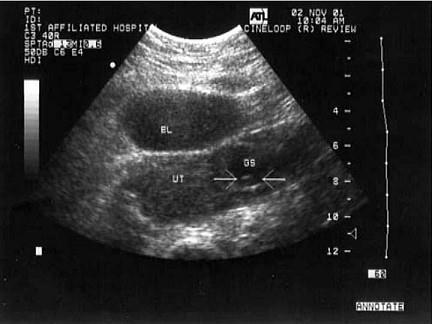

问题 女性,27岁,停经45天,阴道不规则出血1周余。尿妊娠试验阳性。结合超声图像,最可能的诊断为?(?)

选项 A.宫外孕 B.附件炎性包块 C.子宫肌瘤 D.宫腔残留 E.卵巢囊肿

答案 A